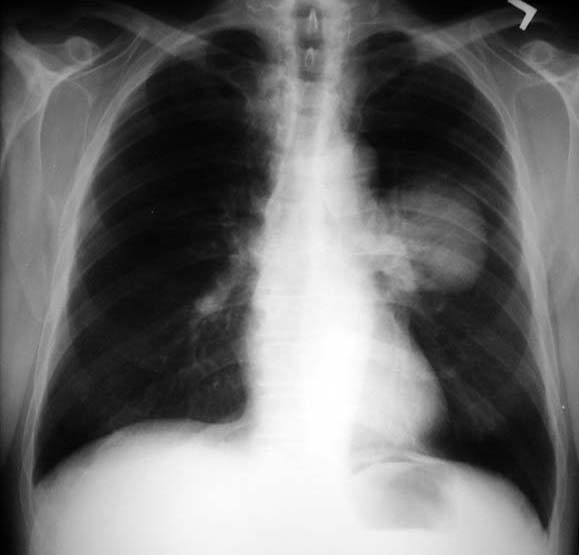

Lung Mass / Cancer Lung

• Round homogenous density

• Sharp margins

• Pulmonary artery overlay sign

• Mass is present in front of the descending left pulmonary artery